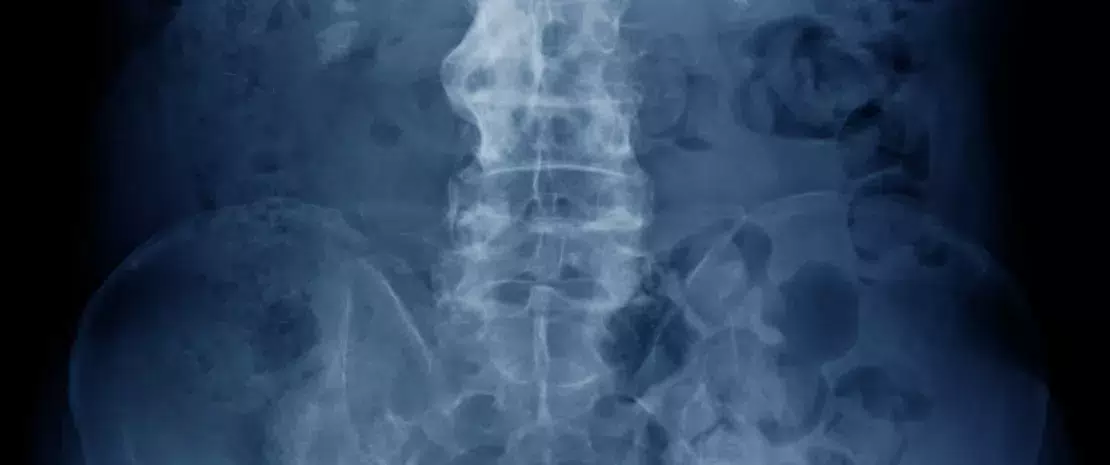

Os autores identificaram também que um tratamento imunossupressor parece poder exacerbar o desequilíbrio da micobiota: a diversidade fúngica diminuiu mais nos oito doentes tratados com etanercept (inibidores da TNF) do que nos cinco doentes com EA que não estavam em tratamento. Contudo, o tratamento com AINEs não levou a mudanças significativas nos nove doentes com EA que foram tratados com estes. Por último, uma correlação positiva forte foi demonstrada entre os níveis de proteína C reativa (PCR), um biomarcador de surtos inflamatórios e a microbiota fúngica. Uma variação na microbiota fúngica (mas não bacteriana) dos doentes com EA foi também associada ao grau da atividade da doença e à intensidade dos danos dos raios-X, sugerindo assim que o micobioma tem um papel fundamental no desenvolvimento de EA. Doentes com EA, especialmente aqueles sem tratamento, apresentaram uma mudança no número e na intensidade de interações entre fungos e bactérias, que poderão estar envolvidos no processo inflamatório. Estas interações foram incidentalmente afetadas pelos tratamentos com AINEs e com imunossupressores.